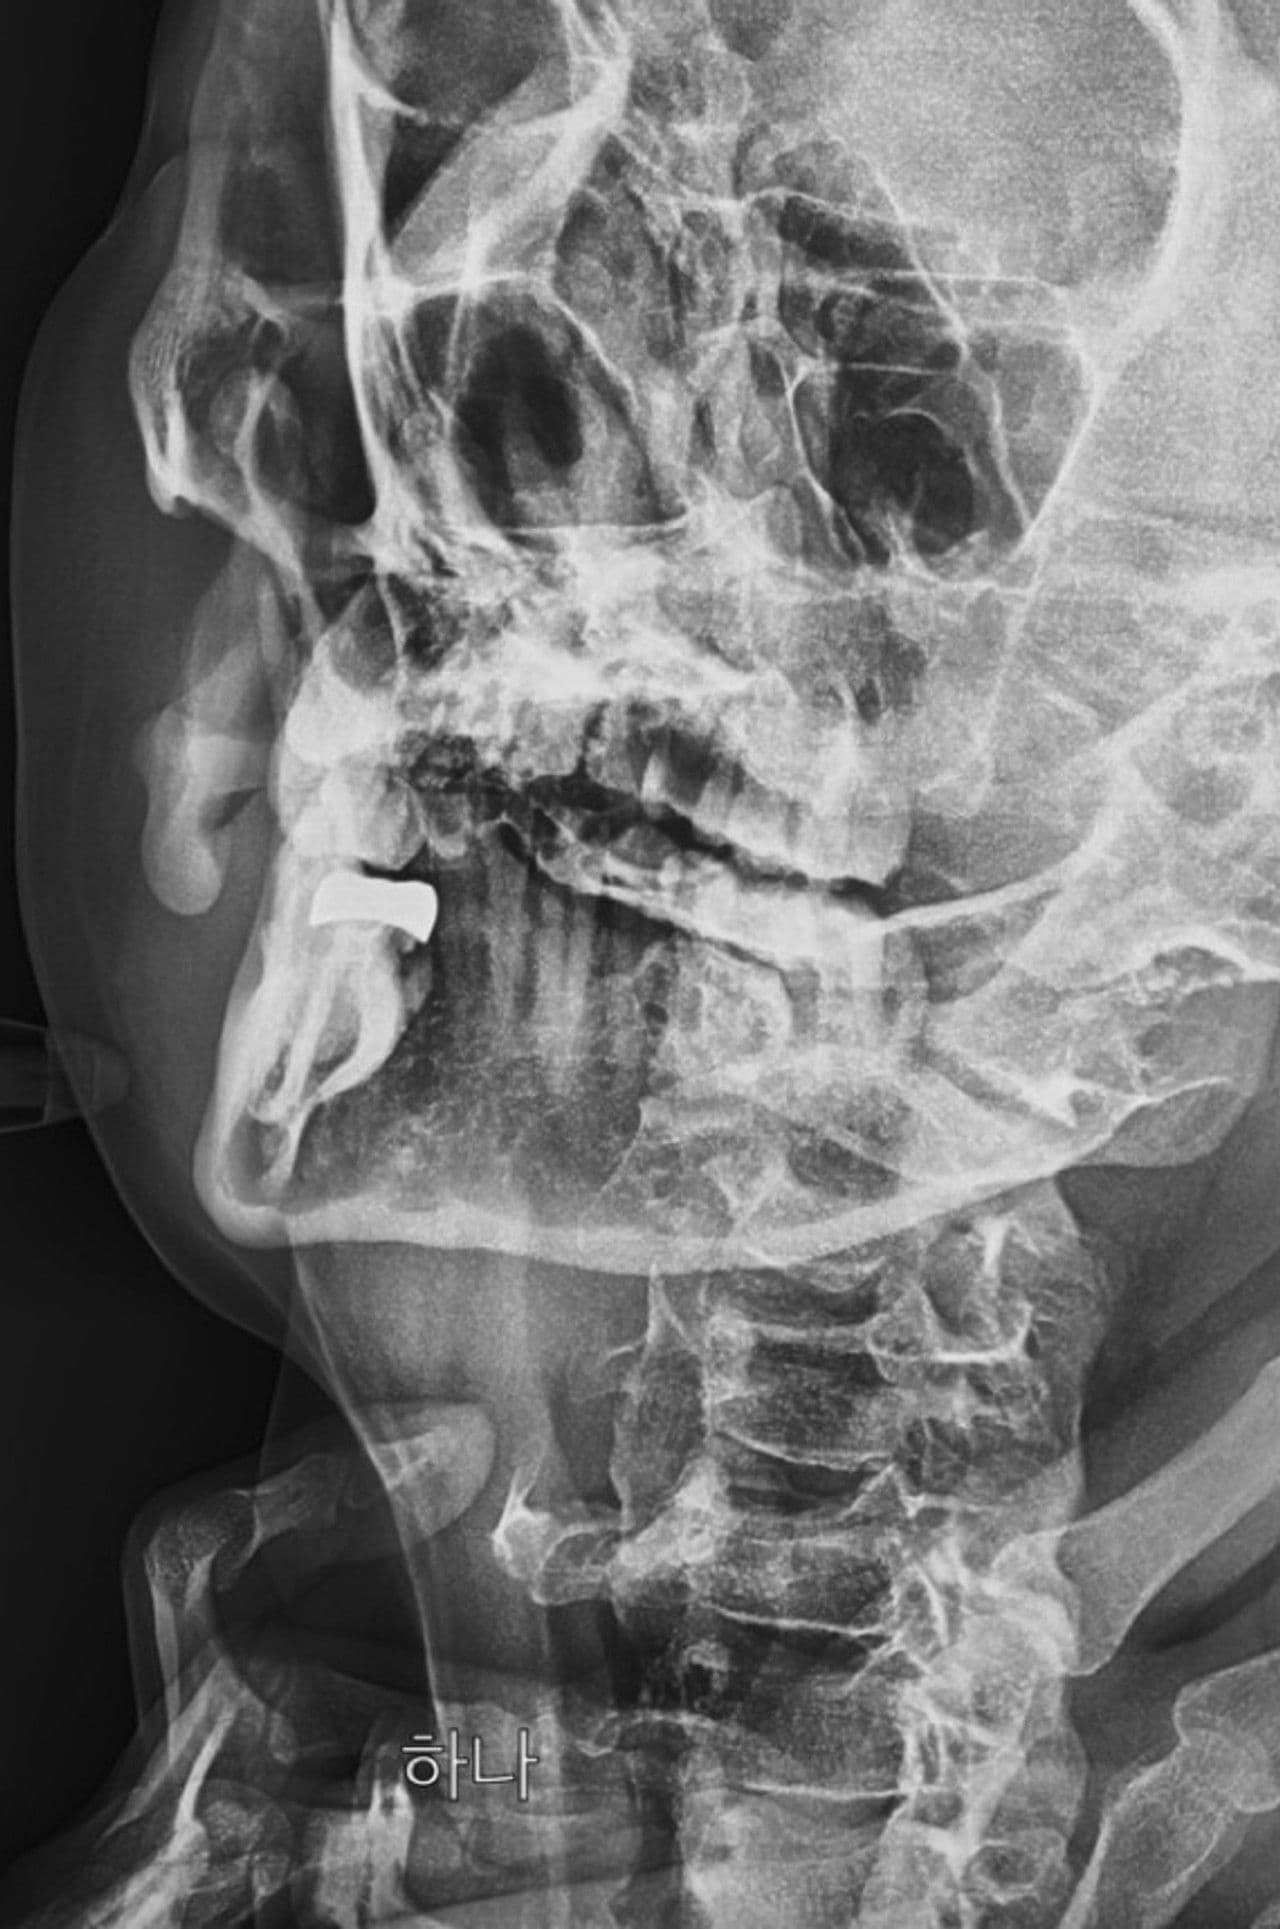

Ray is an experimental film that stages an emotional farce centered around intoxicated figures, juxtaposing the structure of desire with X-ray imagery that exposes and refracts the body.